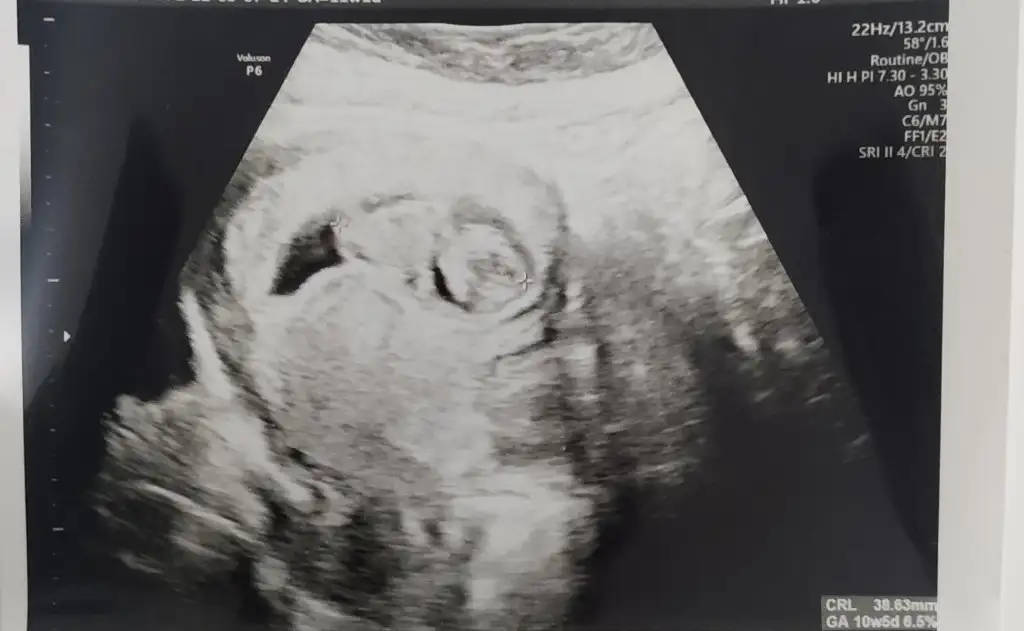

Selam Nursu yeniden biizz😍,bugun Dr gittik ama kendini göstermedi yan döndü hep birde fotoğrafı seninle paylaşmak istedim ,tahminini merak ediyorum😅 13 +2 günlüğüz🤗

20220427_180927.webp